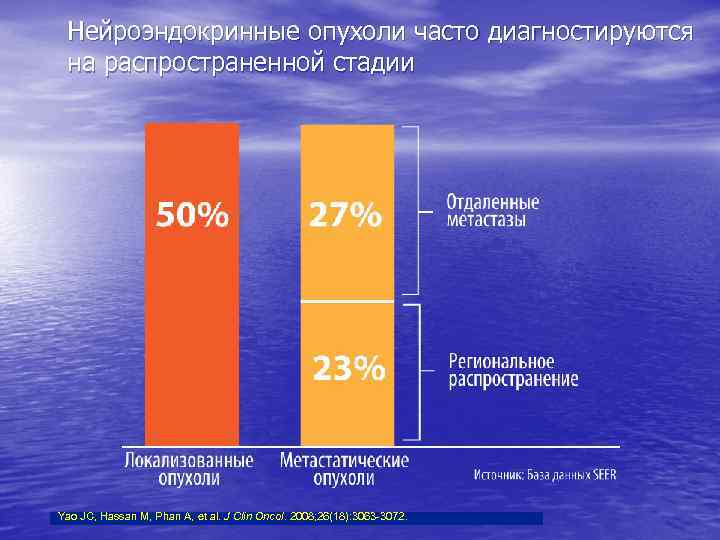

Нейроэндокринные опухоли часто диагностируются на распространенной стадии Yao JC, Hassan M, Phan A, et al. J Clin Oncol. 2008; 26(18): 3063 -3072.